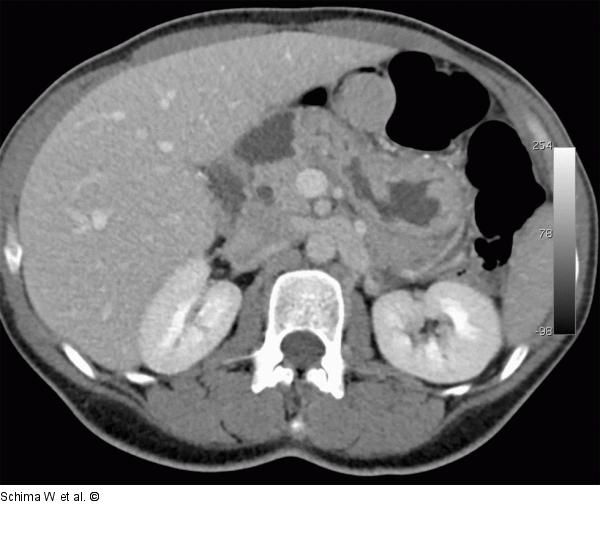

Abbildung 3: MDCT Die MDCT zeigt die Rotation der Mesenterialgefäße (Pfeile), die Stenosierung der V. mes. sup. (Pfeilspitzen) und die abnorme Position der Fußpunktanastomose im medianen Mittelbauch (erkennbar durch das dichte Nahtmaterial), typisch für das Vorliegen einer inneren Hernie. |

Die MDCT zeigt die Rotation der Mesenterialgefäße (Pfeile), die Stenosierung der V. mes. sup. (Pfeilspitzen) und die abnorme Position der Fußpunktanastomose im medianen Mittelbauch (erkennbar durch das dichte Nahtmaterial), typisch für das Vorliegen einer inneren Hernie. |